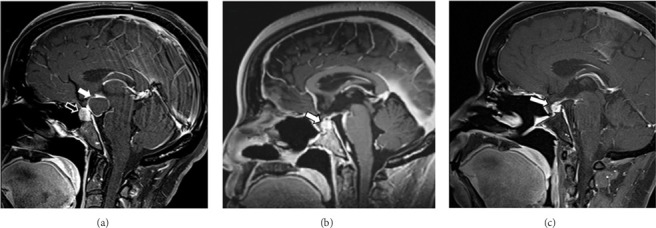

我们报告一个罕见的碰撞肿瘤,涉及垂体大腺瘤和硬瘤性颅咽管瘤在49岁的女性。患者有2年闭经和催乳素升高的病史。脑部MRI显示两个鞍区肿块。由于没有神经功能障碍,最初进行观察,在临床和影像学进展后进行手术切除。病理证实两种肿瘤类型:垂体大腺瘤和硬瘤性颅咽管瘤。术后MRI显示上缘病变残留。患者随后接受了分次立体定向放射治疗残余病变,耐受性良好。

We present a rare case of a collision tumor involving a pituitary macroadenoma and adamantinomatous craniopharyngioma in a 49-year-old woman. The patient presented with a 2-year history of amenorrhea and elevated prolactin. Brain MRI revealed two sellar masses. Initially managed with observation due to the absence of neurological deficits, surgical resection was later performed after clinical and radiographic progression. Pathology confirmed both tumor types: pituitary macroadenoma and adamantinomatous craniopharyngioma. Postoperative MRI showed residual disease at the superior margin. The patient subsequently received fractionated stereotactic radiation for residual disease and tolerated well.